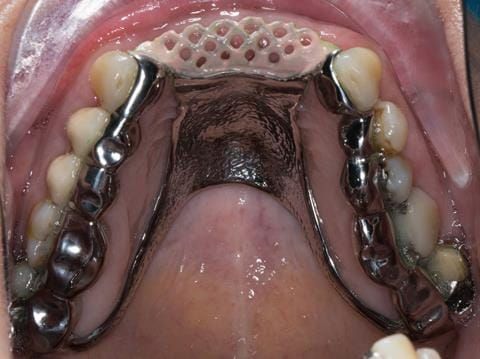

Provision of a maxillary cobalt chromium based partial denture/protective occlusal splint in a heavily restored dentition

- Extract the upper 2-2 teeth and replace with an interim acrylic based partial denture. Reline the interim denture over 9 - 12 months, replacing with a definitive cobalt chromium based partial denture. The definitive denture would ideally be designed as an occlusal protective splint to reduce the the potential for mechanical wear and breakages of the moderately/heavily restored maxillary dentition. In addition, should further upper teeth require extraction they could be added on to the denture cobalt chromium framework - therefore a new prosthesis would not be required as future teeth are lost. This option would produce an excellent aesthetic outcome. This is the option the patient chose to have.

Following consultation and second discussion appointment the patient chose to have option 3 namely, a maxillary cobalt chromium based partial denture/protective occlusal splint. The clinical situation and treatment process is shown in detail below with photographs. The patient was successfully rehabilitated with this and her quality of life considerably improved. The clinical work was provided by Finlay and the technical work by Rowan.